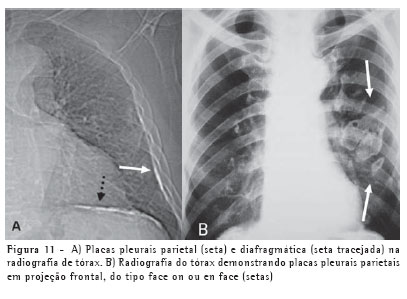

Placas pleuraisAs placas pleurais são a manifestação mais comum da exposição ao asbesto, sendo consideradas marcadores de exposição. Envolvem mais comumente as porções posteriores e laterais da pleura da parede torácica, entre a sexta e a décima costelas, e a pleura diafragmática, principalmente na sua porção superior. A maior parte ocorre na ausência de asbestose e raramente detecta-se asbestose quando placas pleurais não estão presentes. A radiografia do tórax é até hoje o método de imagem mais utilizado na avaliação das placas pleurais (Figura 11).(8-9)

A TCAR é um método mais sensível e específico do que a radiografia. As placas pleurais são caracterizadas na TCAR como espessamentos pleurais focais, geralmente bilaterais, descontínuos, com bordas lisas, em platô, e por vezes com calcificações (Figura 12).(10-11)